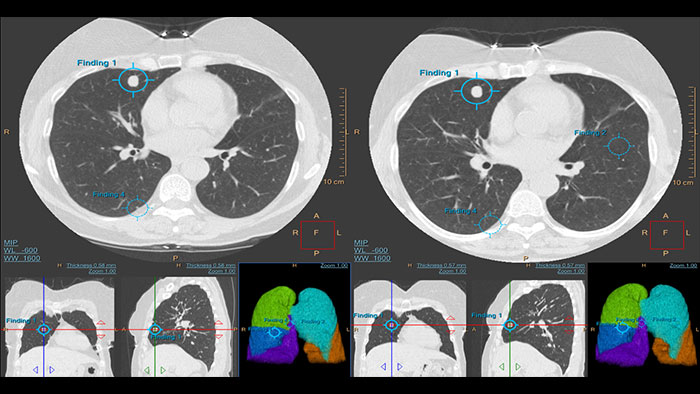

Assessing lung nodules over time

Enables review and analysis of thoracic CT images, providing segmentation, quantification and characterization of physician-indicated lung nodules. The application can be used in both diagnostic and screening evaluations, supporting Low Dose CT Lung Cancer Screening*